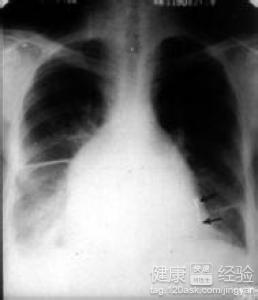

限制型心肌病是什麼原因導致的